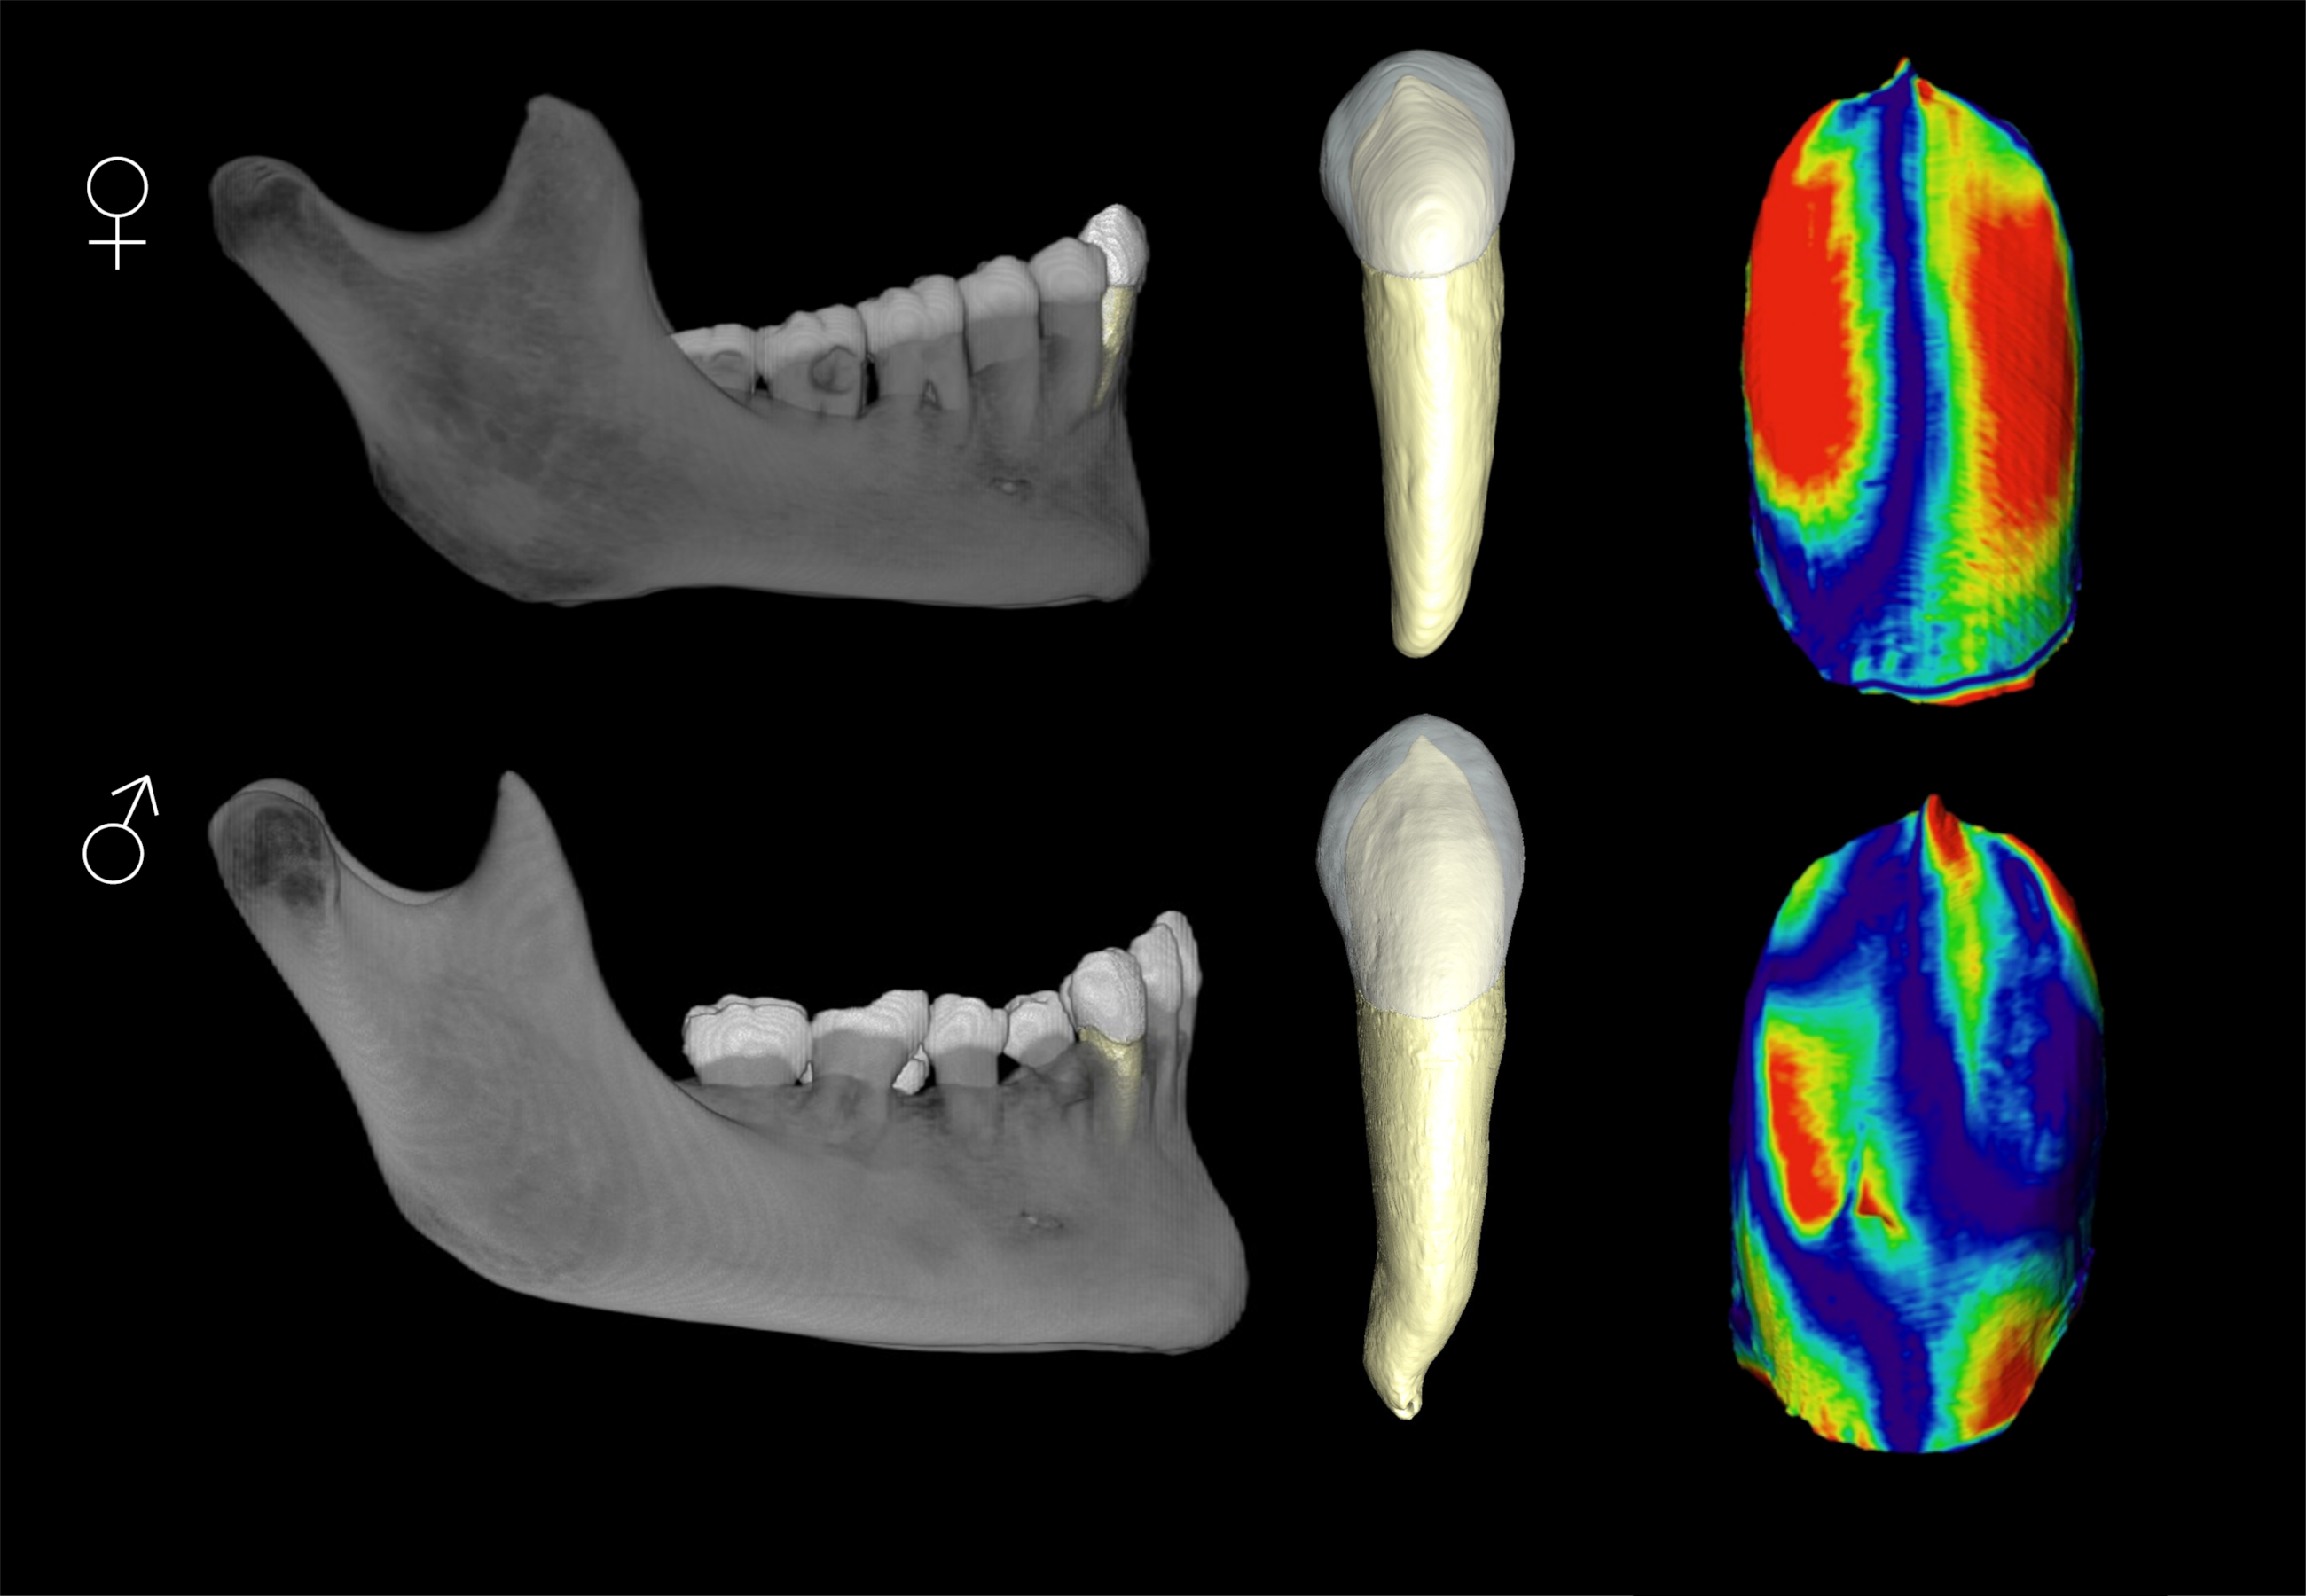

>Sexual dimorphism in humans is so big you can tell the difference between a man and a woman with a single tooth

Why don't brainlets understand the concept of averages? Get a hundred of those images from random people and mix them together. Do you really think it'll be easy?